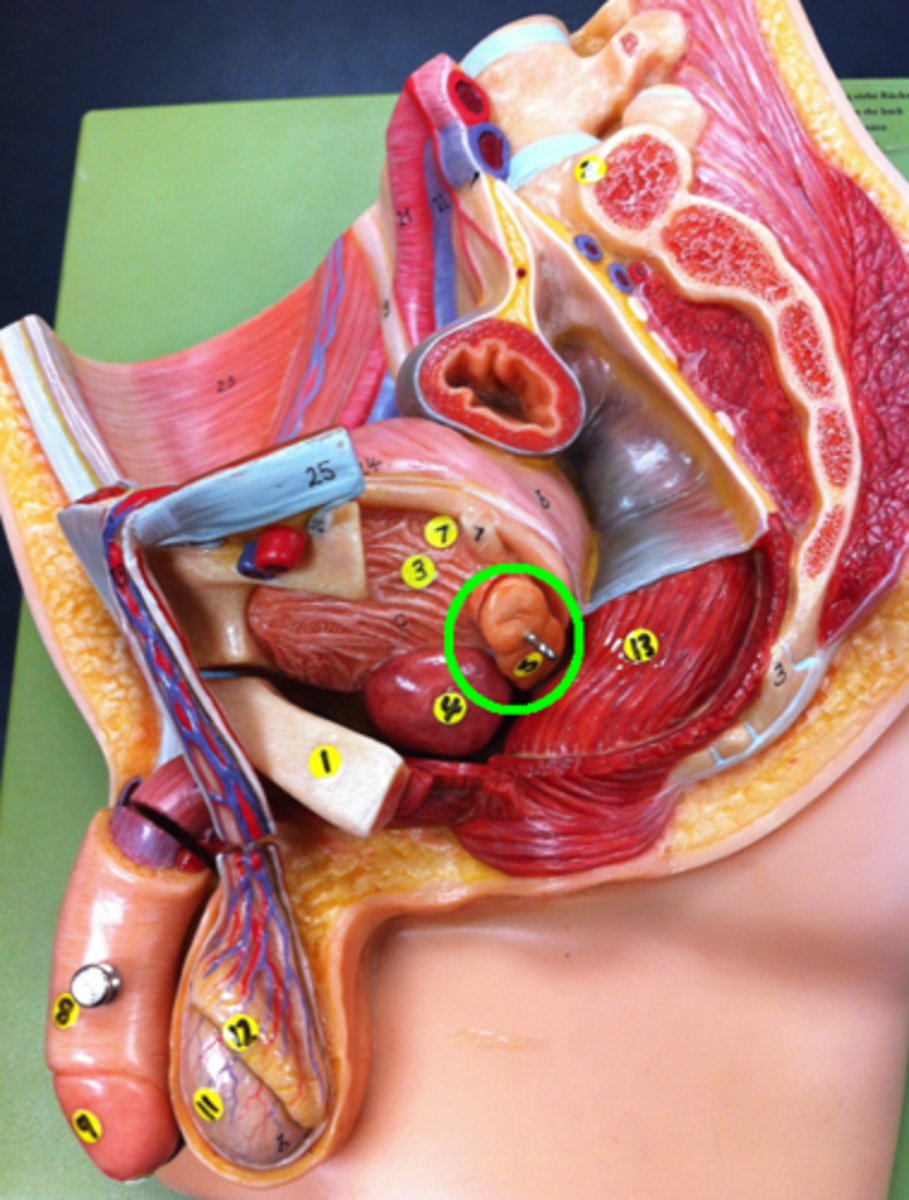

Seminal Vesicle

Ampulla of Ductus Deferens

Ejaculatory Duct leading to the Prostatic Urethra